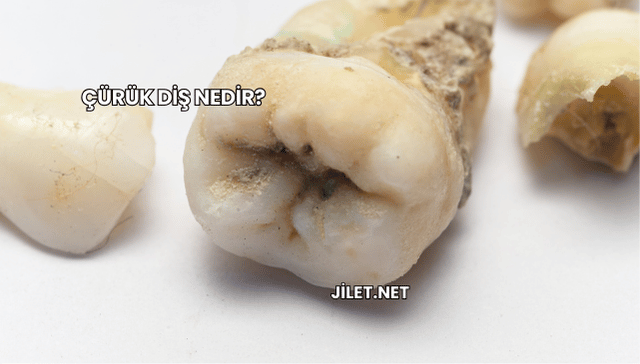

Çürük diş, diş minesinin asit üreten ağız bakterileri tarafından zamanla aşındırılması sonucu oluşan yaygın bir sorun olup erken dönemde tespit edilmediğinde sinir dokusuna kadar ilerleyerek şiddetli ağrı ve enfeksiyonlara yol açabilir. Bu yazıda çürük dişin tanımı, nedenleri, belirtileri, tedavi yöntemleri ve koruyucu önlemler ele alınarak kapsamlı bir bakış açısı sunuluyor.

Çürük diş, diş yüzeyindeki plakların asit salınımıyla mine dokusunu zayıflatması sonucu oluşur ve şekerli gıdaların tüketimi, yetersiz ağız hijyeni ile birleştiğinde diş yapısındaki mineral kaybını hızlandırarak çürüme sürecini tetikler.

Görsel değişiklikler

Çürük alanları diş yüzeyinde kahverengi veya siyah lekeler oluşturabilir ve ışık altında mat görünümle ayrışır.